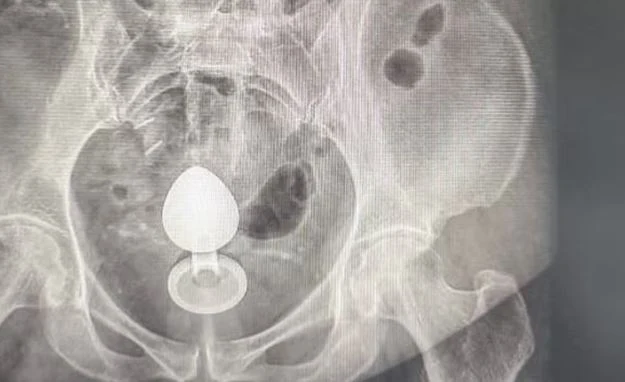

O caso foi atendido pelo cirurgião coloproctologista Daniel Brosco. Segundo o médico, a paciente contou que, na verdade, estava usando o sex toy para ajudar com a constipação intestinal, e não com finalidade sexual. O médico alerta que isso é contraindicado.

“A paciente contou que colocou o objeto no ânus por volta das 7h. Pouco mais de duas horas depois, ao sentar, percebeu que ele tinha subido e precisou buscar atendimento médico”, explica o médico.

O médico explica que a paciente tinha um quadro de pólipos no intestino — quando a mucosa apresenta um crescimento anormal que pode evoluir para câncer. Com isso, a parede intestinal era mais sensível, aumentando o risco de perfuração.

Brosco afirma que ela passou pelo procedimento para retirada do objeto e passa bem, mas que o caso é um alerta sobre o uso desse tipo de brinquedo. O uso inadequado pode levar a complicações como lacerações, sangramentos e perfurações intestinais — especialmente em pacientes com condições prévias que tornam a mucosa mais sensível.